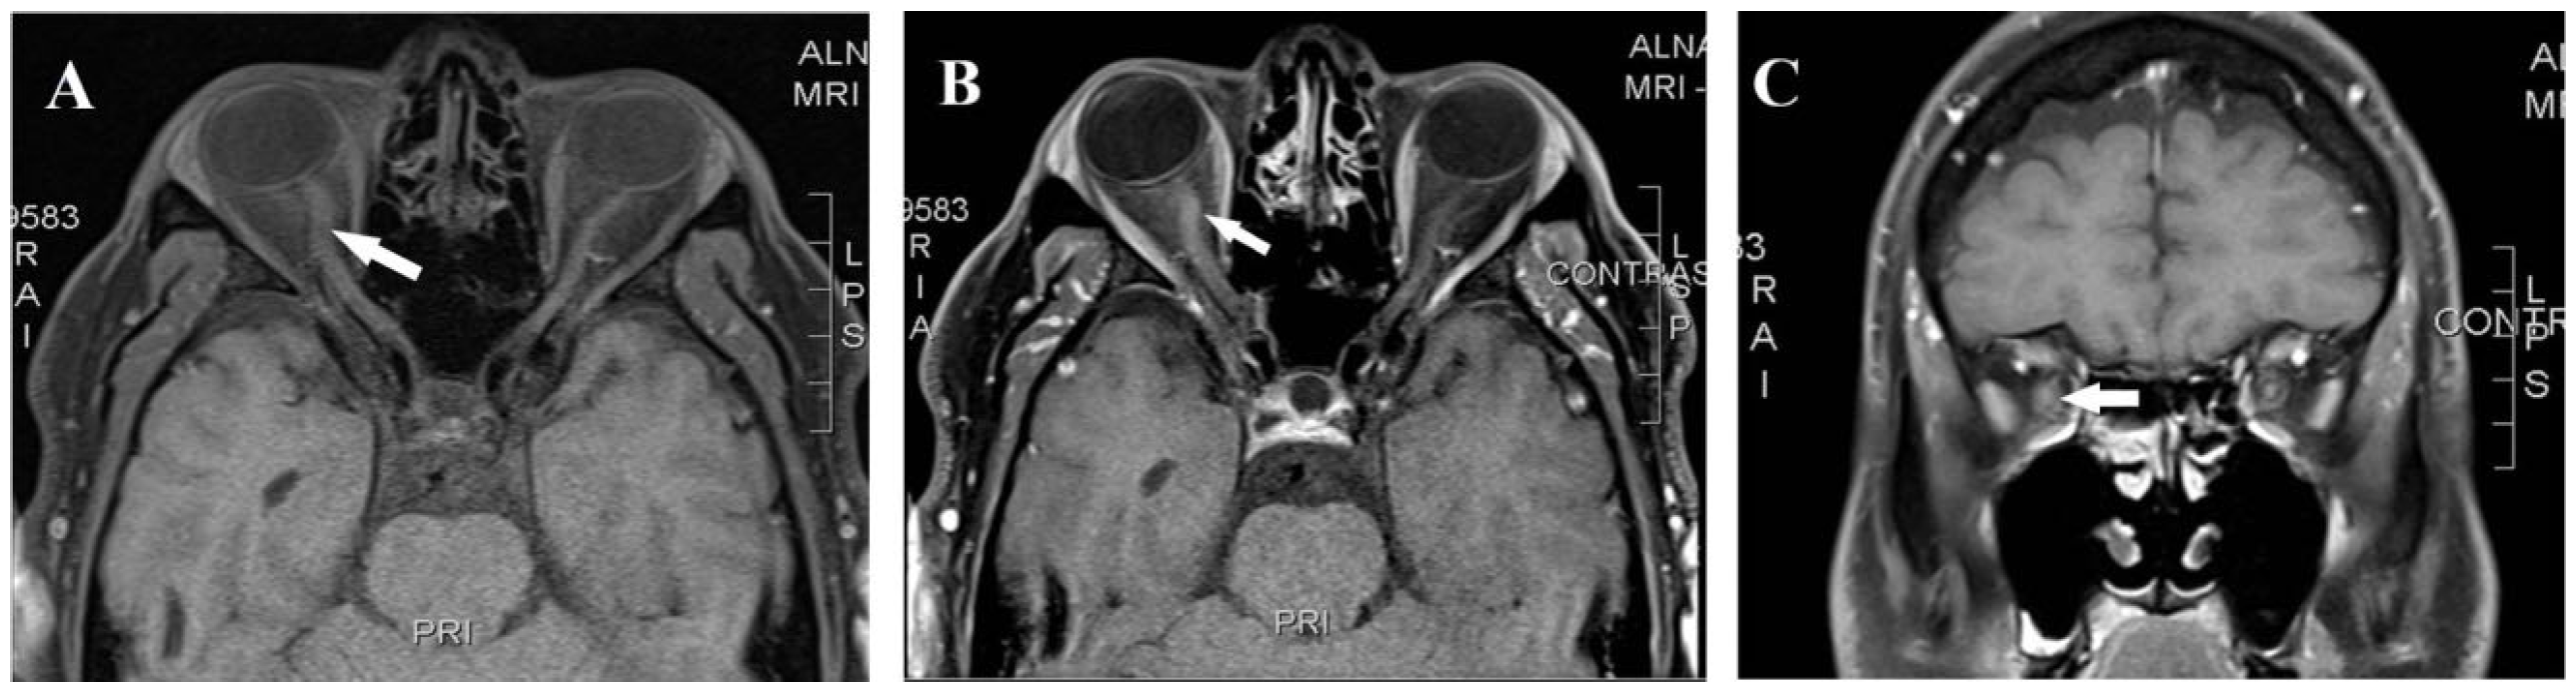

| Present Case | 42/M | m.11778G>A (MT-ND4) | Painful acute ON sequential involvement over 1 year | Right-optic-nerve enhancement, no brain MS lesions; later thoracic T11 myelitis; normal brain MRI | Initial CSF normal; later OCBs positive | Rituximab, idebenone | Unique sequence: LHON genetically confirmed before demyelinating event; MRI enhancement atypical for LHON |